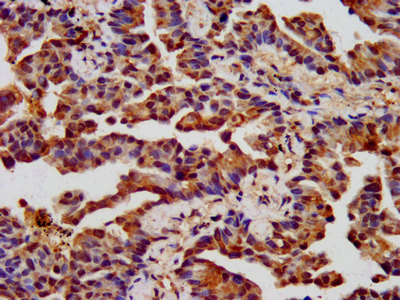

IHC image of CSB-PA005397LA01HU diluted at 1:400 and staining in paraffin-embedded human lung cancer performed on a Leica BondTM system. After dewaxing and hydration, antigen retrieval was mediated by high pressure in a citrate buffer (pH 6.0). Section was blocked with 10% normal goat serum 30min at RT. Then primary antibody (1% BSA) was incubated at 4°C overnight. The primary is detected by a biotinylated secondary antibody and visualized using an HRP conjugated SP system.